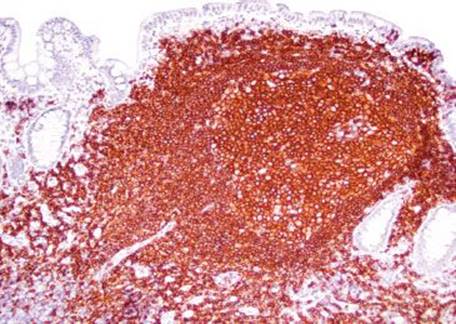

Answer: You are not alone! Prominent lymphoid aggregates can be especially alarming in the terminal ileum and, thus, are a common source of consultation. The small bowel serves as an essential component of the immune system through its perpetual surveillance of the passing luminal contents. Diligent immunosurveillance is facilitated through specialized epithelial cells (M-cells) that transport luminal antigens to the lymphoid aggregates (designated “Peyer patches” when seen in the terminal ileum). Hyperplastic lymphoid aggregates can be sufficiently large as to be visualized endoscopically and can also serve as intussusception lead points, especially in young children.5,6 The epicenter of lymphoid aggregates is in the mucosa but especially prominent cases can feature extension into the submucosa, raising concerns for a hematolymphoid malignancy. Histologic features reassuring for a benign, reactive process include the presence of germinal centers, tingible body macrophages, and a polymorphous constituent lymphoid population (i.e., a variety of cell sizes represented); however if the focus in question seems at all concerning, a quick immunohistochemical panel may be worthwhile (Figs. 3.19–3.37) (Table 3.1).

Figure 3.32 Normal terminal ileum (CD23 immunostain). A CD23 highlights the follicular dendritic cell meshwork surrounding the germinal centers, a feature of intact (normal) lymphoid aggregate architecture.

Figure 3.33 Normal terminal ileum (CD3 immunostain). A CD3 highlights T lymphocytes, which are predominantly seen surrounding the germinal center. On H&E, these lymphocytes were uniform and small, no atypical cytologic features were seen.

Figure 3.34 Normal terminal ileum (CD20 immunostain). A CD20 highlights B lymphocytes, which are the majority of the lymphoid constituents.

Figure 3.35 Normal terminal ileum (BCL-6 immunostain). Various artifacts occasionally make germinal centers difficult to discern. In such cases, BCL-6 and CD10 are equally helpful markers that highlight germinal centers.

Figure 3.36 Normal terminal ileum (CD10 immunostain). Like BCL-6, CD10 also highlights germinal centers. Of note, CD10 also highlights a crisp/intact brush border characteristic of normal small bowel mucosa (bracket). Defective, broken, or smudgy brush borders should prompt consideration of microvillous inclusion disease, especially in infants.

Figure 3.37 Normal terminal ileum (BCL-2 immunostain). Normal germinal centers are BCL-2 negative. If the germinal center is BCL-2 reactive, consider follicular lymphoma, which is characterized by the t(14;18) rearrangement of BCL-2 and the immunoglobin heavy chain (IgH). Importantly, recall that normal B lymphocytes in the mantle zone surrounding the germinal center and normal T lymphocytes express BCL-2. Therefore, interpretation of BCL-2 always requires concomitant interpretation of CD20 B lymphocyte marker, CD3 T lymphocyte marker, and a germinal center marker (BCL-6 or CD10).